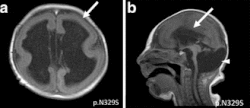

Diagnosis

Microlissencephaly can be diagnosed by prenatal MRI.[30] MRI is better than ultrasound when it comes to detecting microlissencephaly or MSGP prenatally.[34] The ideal time for proper prenatal diagnosis is between the 34th and 35th gestational week which is the time when the secondary gyration normally terminates. In microlissencephaly cases, the primary sulci would be unusually wide and flat while secondary sulci would be missing.[35]